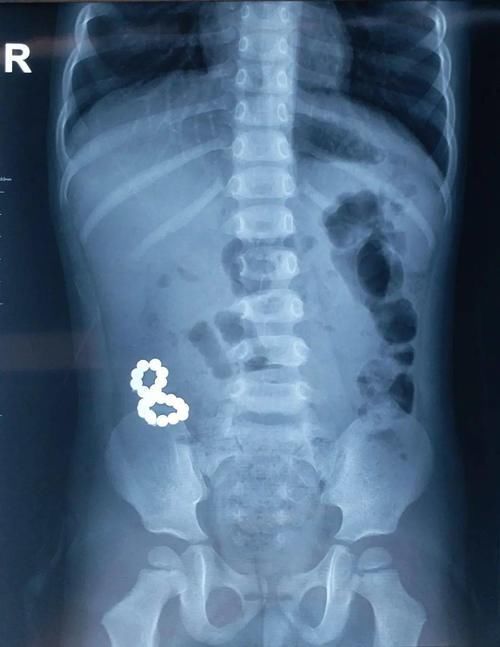

这不,接近年底,来自甘肃九岁的兰兰,在“尝尝五彩豆味道”这样幼稚想法的趋使下,经口吞进近30枚磁力珠。吞入异物后的兰兰以“腹痛1天”就诊当地医院,医生建议先观察保守治疗,等待磁力珠自行排出。结果家长仍抱着“等等就能排出来”的想法居家等待了20多天却迟迟未见排出,这才连夜租车风风火火地跨越两省多市来到了西安市儿童医院普外二科。

接诊的宋医师检查了兰兰的腹部体征,结合查体及检查,考虑已经有消化道穿孔形成内瘘可能,及时安排了手术。术中探查见兰兰小肠多处穿孔形成内瘘。